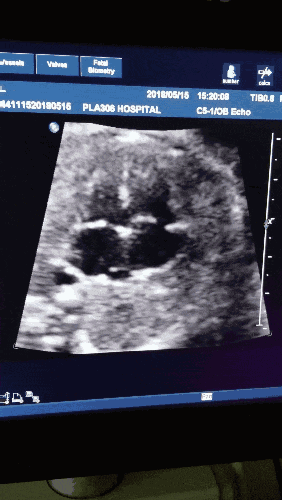

J'ai passé une échographie à la 14e semaine et tout était normal, mais le rythme cardiaque du fœtus était faible, à peine supérieur à 90, et le médecin a dit : "Ce rythme cardiaque fœtal est trop lent", que dois-je faire ?

Vous en êtes maintenant à 14 semaines de gestation, c'est-à-dire au milieu du trimestre. 90 battements de cœur du fœtus, c'est définitivement en dehors de la plage normale, mais ce qu'il faut faire ensuite, c'est laisser la nature suivre son cours, il ne sert à rien de traiter ou d'intervenir, vous pouvez revoir l'échographie après une semaine. Si le fœtus se développe normalement, continuez à l'observer. Si le fœtus n'est pas en bon état, l'avortement sera pratiqué.

Bien qu'il soit dit que le cœur du fœtus peut être entendu à l'aide d'un stéthoscope dans l'abdomen de la femme enceinte à partir de la 17e semaine de grossesse et que, dans une grossesse normale, la première surveillance des battements du cœur du fœtus se fait en principe après la 30e semaine de grossesse, il n'en est rien. Cependant, dans le cas d'une grossesse normale, les bourgeons fœtaux dans la cavité utérine et les pulsations du tube cardiaque fœtal sont visibles à l'échographie après 42 jours de ménopause. Même si l'ovule fécondé est en retard, les battements du cœur du fœtus sont visibles dans l'utérus à l'échographie au plus tard 56 jours après 49 jours de ménopause. Si aucun battement de cœur ou bourgeon fœtal intra-utérin n'est visible au-delà de 56 jours après l'arrêt des règles, le diagnostic d'insuffisance fœtale est en principe posé. La plupart du temps, les battements du cœur du fœtus sont visibles sur l'écran de l'échographie à 6-7 semaines de grossesse, mais ils sont si faibles qu'il est presque impossible de les entendre si on les écoute à l'aide d'un stéthoscope. En particulier, il faut attendre près de 16 semaines de grossesse pour surveiller le cœur du fœtus à l'aide d'un stéthoscope, surtout avec un moniteur cardiaque fœtal utilisé à la maison. À 14 semaines de grossesse, le rythme cardiaque du fœtus à l'échographie n'est que d'environ 90 par minute, ce qui est effectivement trop lent et nécessite un examen plus approfondi par le médecin pour déterminer si le fœtus souffre d'hypoxie ou d'autres problèmes. Un rythme cardiaque fœtal normal devrait être d'au moins 120 battements par minute, et même s'il est un peu plus lent, il ne devrait pas être inférieur à 110 battements par minute.